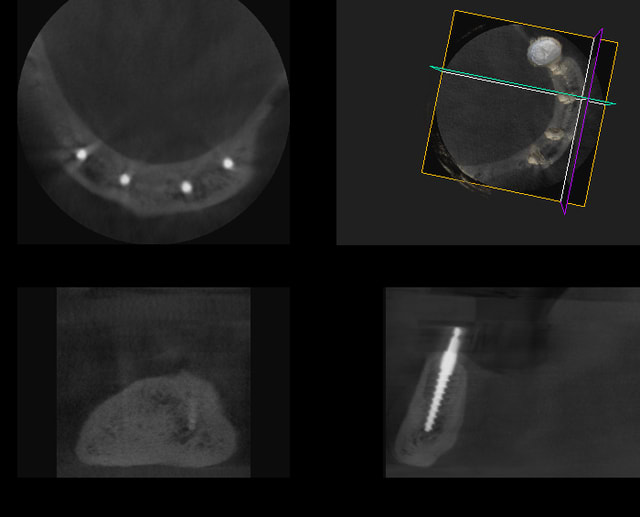

ta remarque est très bien, il est vrai qu il semble que ca soit trop lingual les deux implants au centre, mais ils sont placés juste au milieu de l´os ( radio DVT). je suis d accord avec toi ca serait un problème grave si les implants étaient placés dans la muqueuse mouvable buccale de l os, mais dans la muqueuse mouvable linguale il n y a pas de problème pour les patients le but étant de forer au milieu de l os, ceci dit si l os avait éte configuré autrement et que je n aurai donc pas du forer à cette endroit j aurai préféré car il y a meilleur comme configuration ...

pour montrer mieux, j ajoute deux cas . Le premier cas ( première photo)les implants en position 34 et 42 sont fait par un dentiste assistant et les implants 32 et 44 par un chirurgien dans notre clinique (pendant un cours) , après l opération on a fait un DVT ,Où tu peux voir que le chirurgien a trouvé mieux le miieu de l´os et que l os buccal est plus fort...

Le deuxième cas, tu connais déjà : l os "sacré" est assez "fort" dans la radio.